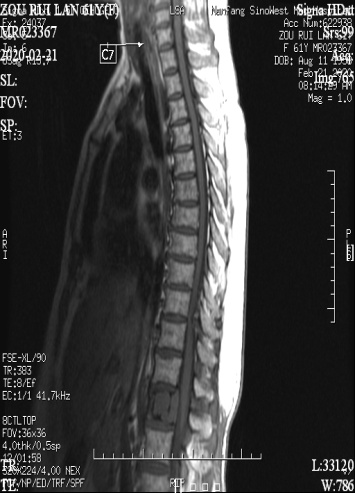

图左:术前MR示腰椎肿瘤(圆圈处)、胸椎狭窄(箭头所指)

图右:术后X光,病变脊椎切除,代以人工椎体。